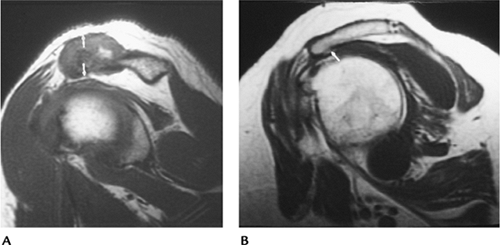

FIGURE 7-16 Impingement syndrome. (A) Sagittal T1-weighted MR image showing hypertrophy of the AC joint (arrows) reducing the humeroacromial space. (B) Sagittal T1-weighted MR image showing an anteriorly angulated acromion with an inferior osteophyte (arrow) causing impingement.